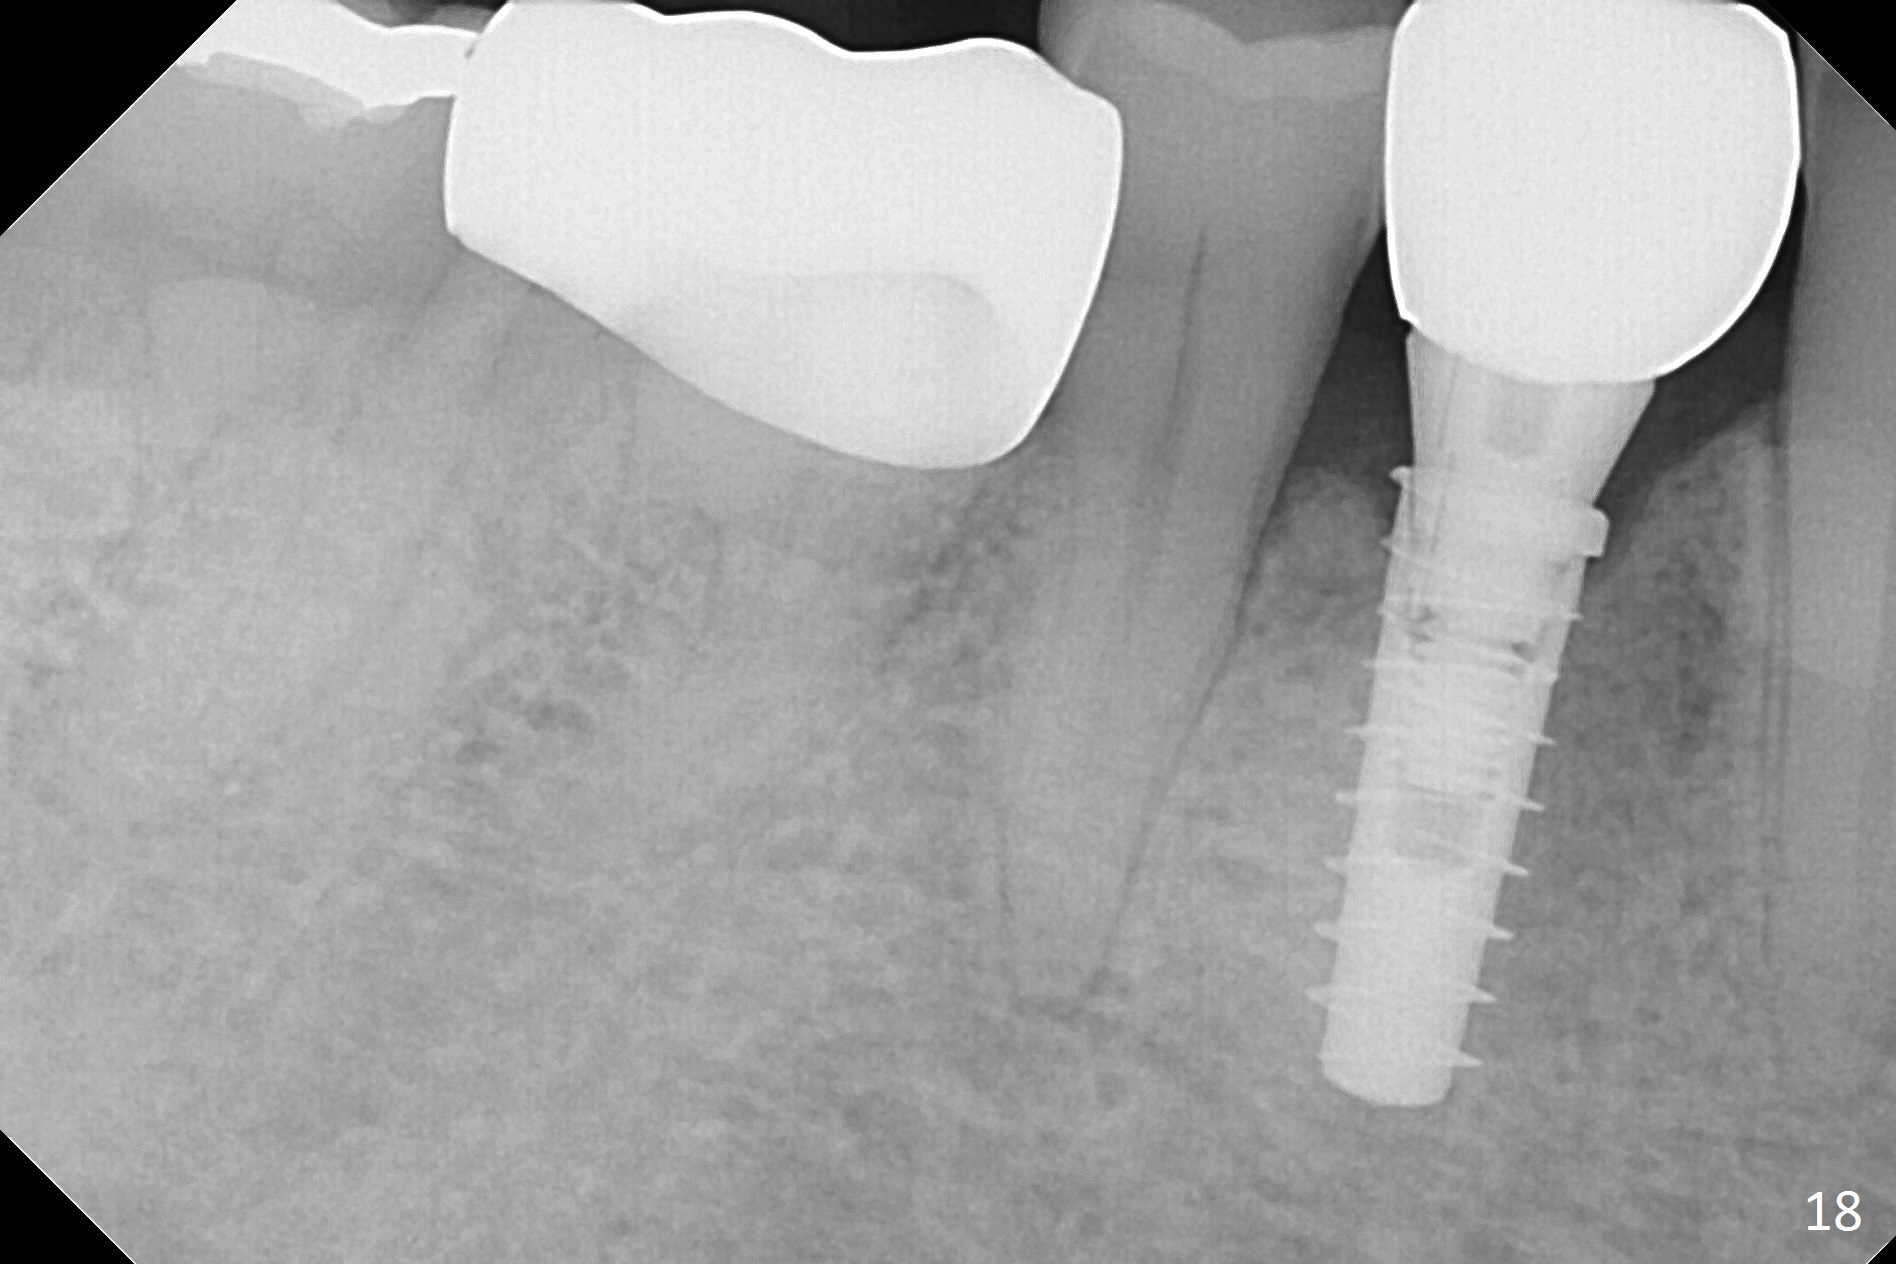

The right posterior final restorations (Fig.14) are fabricated as planned: increase in vertical height (Fig.15). The increase is minimal (Fig.14, 17(#2 limited crown height), 16 (#2 crown being thin *)). Fig.17,18 are taken immediately post cementation. There is no bone loss 10 months post cementation (Fig.19,20). The gingiva is healthy around the implant crowns (#2, 4 and 28) 1 year 4 months post cementation (Fig.21,22).